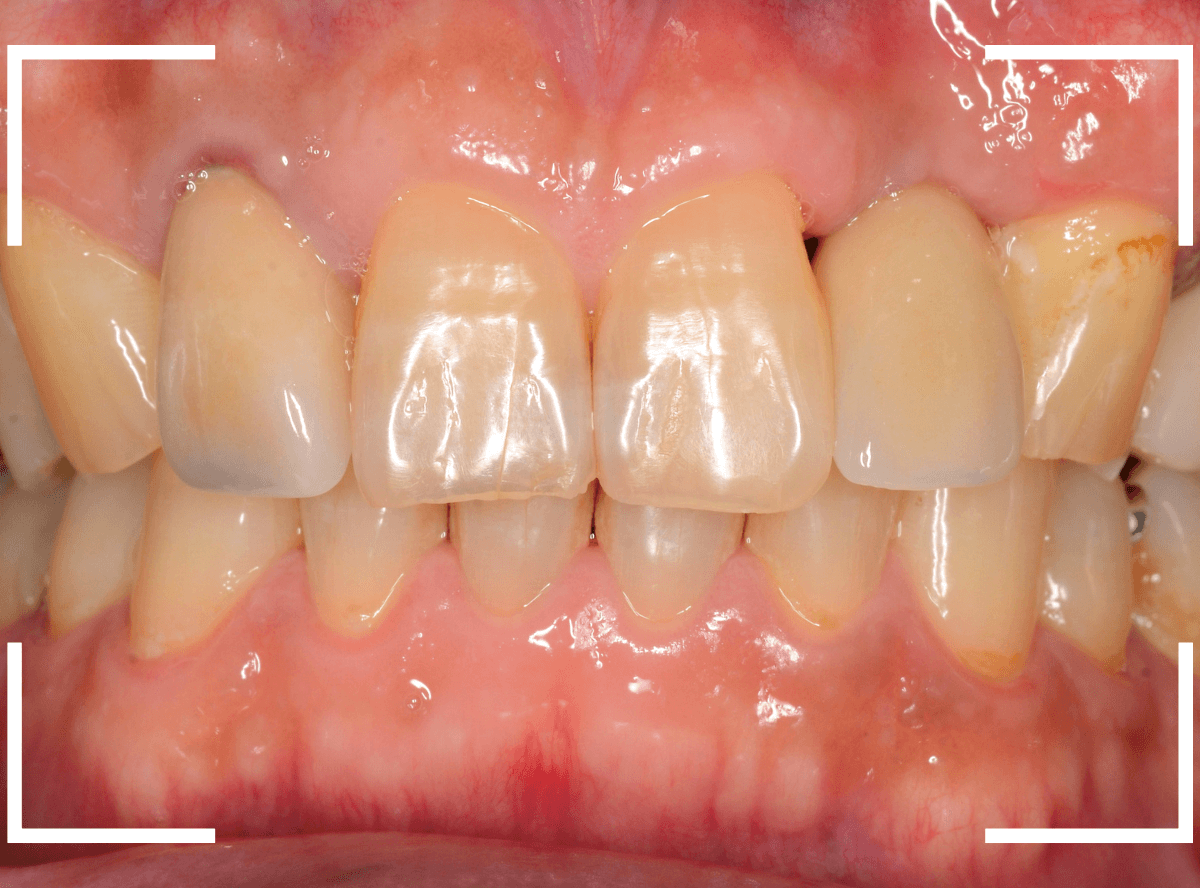

手術当日、インプラント体を埋入した直後です。

この状態で、しばらく経過観察をします。

インプラント体の周囲の骨と歯肉が落ち着くのを待って、型取りをします。

模型上で精密にインプラントを製作します。

インプラントset後の状況です。

審美的にも、満足いただける仕上がりになりましたが、現在の状況を維持するために治療後の定期メンテナンスが不可欠になります(インプラントに限りませんが)。